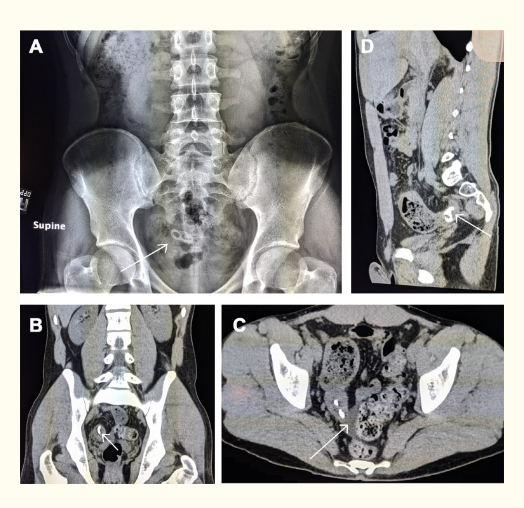

图1.腹部成像。(A)腹部平片。一个2.4×1.2 cm的长方形放射密度,其中两个透明区域位于骨正中线的正央。(B)腹部/骨盆CT。回肠远端可见2.4厘米的高密度。(C)腹部/骨盆CT,轴向切片。回肠远端可见2.4厘米的高密度。粪便充满扩张的回肠末端,右结肠增厚,相邻绞股。刚好在这个充满粪便的扩张性回肠末端附近发现了高密度。少量骨盆液(箭头)。(D)腹部/骨盆CT。回肠远端可见2.4厘米的高密度。回盲肠交界处增厚,右结肠增厚。